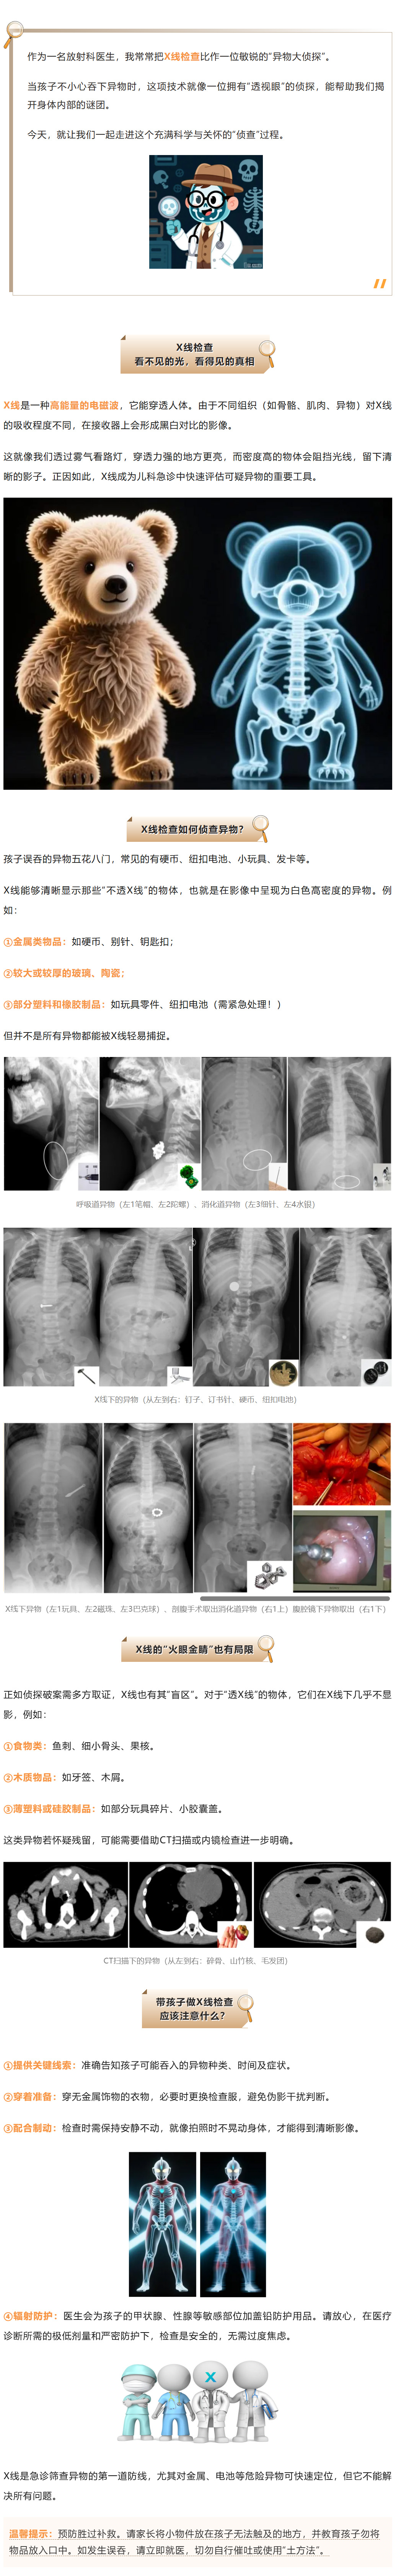

硬币、电池、小玩具…孩子吞下的异物,在X线下竟然是这样!